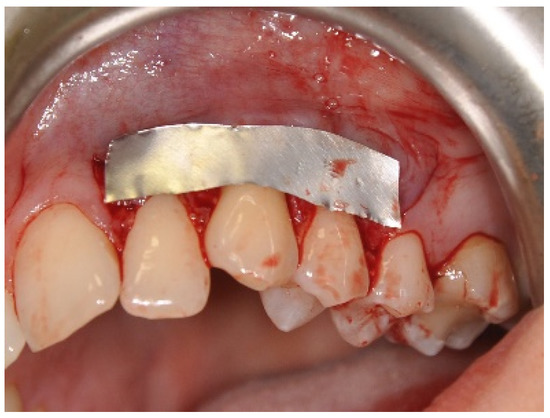

2.3. Surgical Procedures

Surgical Procedure Using Biokol®, the Xenogeneic Lyophilized Collagen Sponge